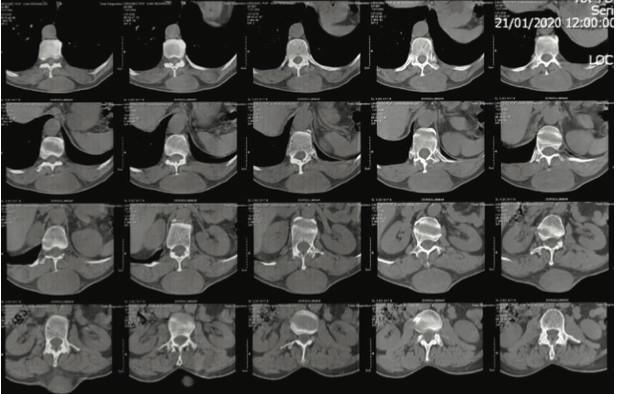

Tomografía de columna dorsolumbar: se evidencia co- lección liquida a nivel de tejidos blandos subcutáneos posterior de la región dorso lumbar de T10 a L1 de 7.3x3.9x12.4cm con un volumen de 184cc. Los bordes son bien definidos y las paredes son delgadas, con un gro- sor de 2.3mm, los cuales, tras la aplicación de medio de contraste, muestra realce sugestivo. No hay invasión de estructuras óseas o músculos paravertebrales (figura 2).